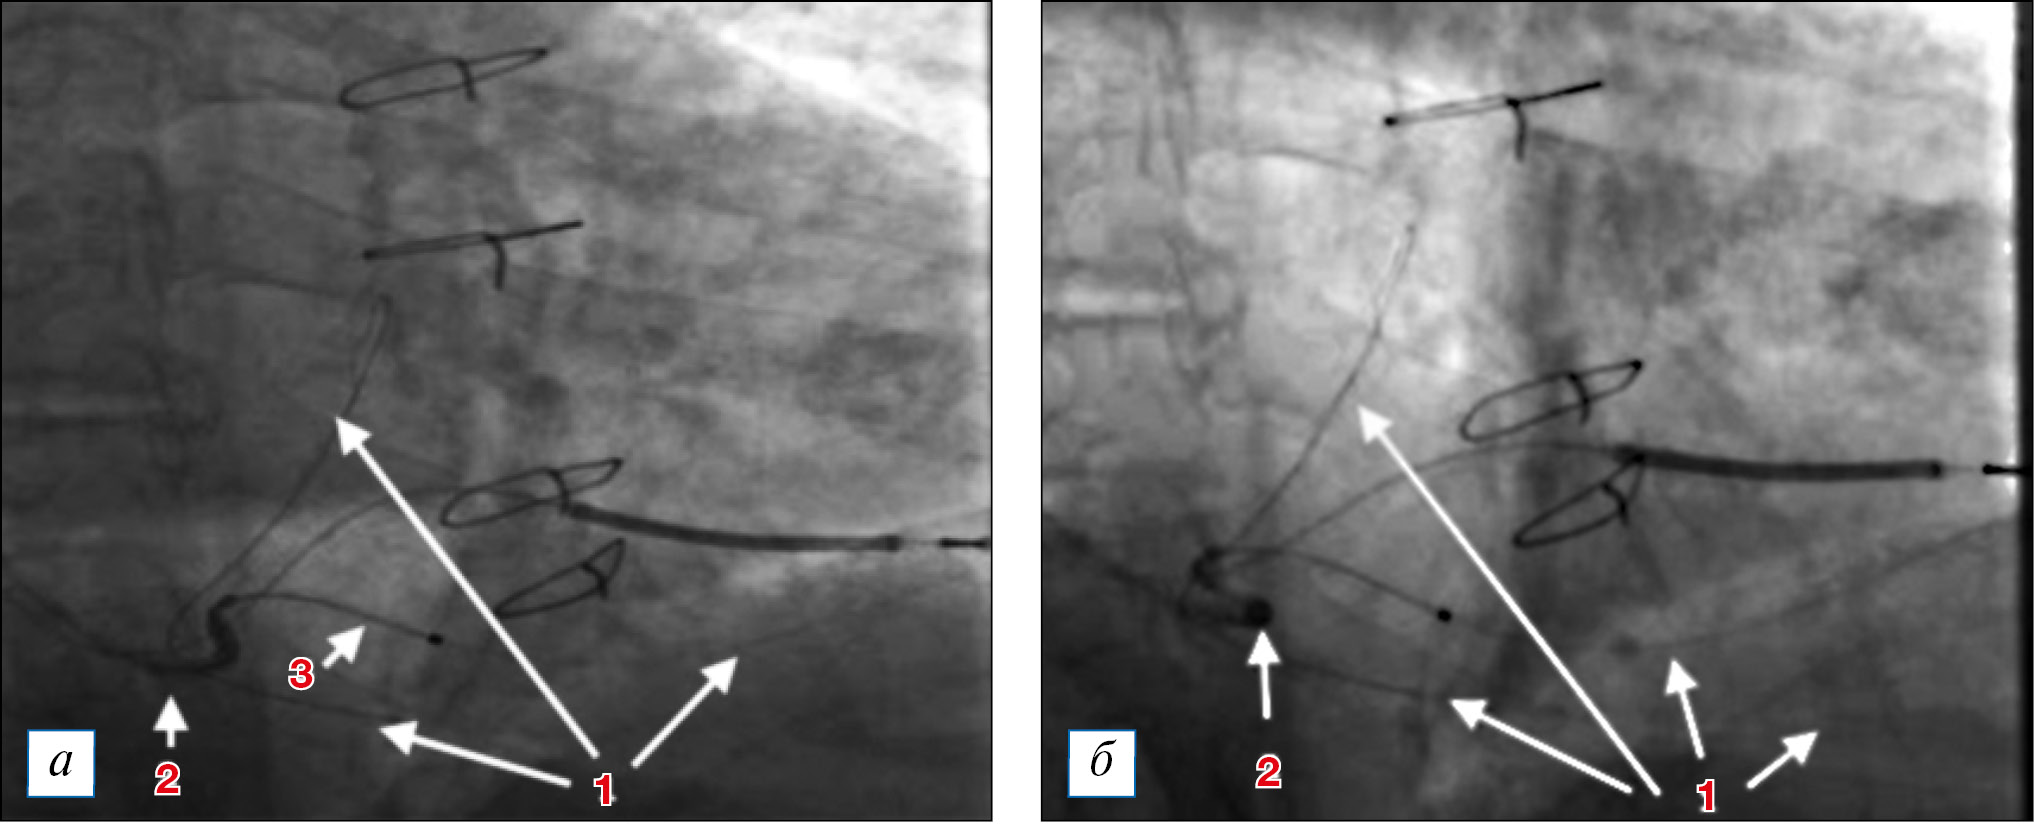

Для имплантации левожелудочкового электрода была выбрана заднелатеральная вена сердца. При попытке проведения проводника в заднелатеральную вену проводник заходил туда на глубину около 1 см мягкой частью дистального конца, и при дальнейшем продвижении жесткая часть дистального конца проводника увлекала за собой весь проводник в основное русло большой вены сердца. Для проведения проводника был успешно применен субселективный катетер с изогнутым концом, по которому коронарный проводник введен в заднелатеральную вену до ее дистальных отделов. При этом в дистальном отделе была найдена коллатераль со средней веной сердца, через которую проводник для большего упора введен в среднюю вену сердца, проведен по ней ретроградно и выведен в большую вену сердца. На данном этапе в большинстве случаев удается провести электрод по проводнику без значимых трудностей. Тем не менее при попытке провести электрод, он встречал сопротивление в области дефекта наполнения, петлей упирался в изгиб вены и, как следствие, не продвигался на нужную глубину в вену, выталкивая при попытке поступательного ортодромного продвижения систему доставки в противоположном направлении (рис. 2). Использовать противотракцию расположенного внутри электрода коронарного проводника не удавалось, так как вместо продвижения электрода вперед отмечалось лишь ретроградное вытягивание коронарного проводника. Позиционирование нескольких коронарных проводников для выпрямления вены также не дало результатов.

Рис. 2. Установленная система доставки. Проведение коронарного проводника в заднелатеральную вену (правая косая проекция, 30°): 1 — коронарный проводник, проведенный через селективный интродьюсер (2) в заднелатеральную вену, идущий через коллатераль в среднюю вену сердца и возвращающийся ретроградно в большую вену сердца; 2 — система доставки левожелудочкового электрода с установленным внутри селективным катетером, заходящим в устье заднелатеральной вены сердца (обращает на себя внимание выход селективного катетера из устья на панели 2б при попытке поступательного продвижения электрода по коронарному проводнику); 3 — электрод, проводимый по коронарному проводнику. / Fig. 2. Positioning the left ventricular lead delivery system into the coronary sinus. Passage of the coronary guidewire into the posterolateral vein (right anterior oblique projection, 30°): 1 — coronary guidewire has been introduced into the posterolateral vein with the help of a subselective catheter (2). The guidewire went through the collateral vein into the middle cardiac vein and returned in a retrograde manner to the great cardiac vein; 2 — the left ventricular lead delivery system with a subselective catheter inside. The tip of the subselective catheter was localized in the orifice of the posterolateral vein. It is remarkable, that during the attempts of pushing the left ventricular lead along the guidewire, the subselective catheter fell out of the posterolateral vein orifice (panel 2б); 3 — the left ventricular lead, that was passed along the guidewire.